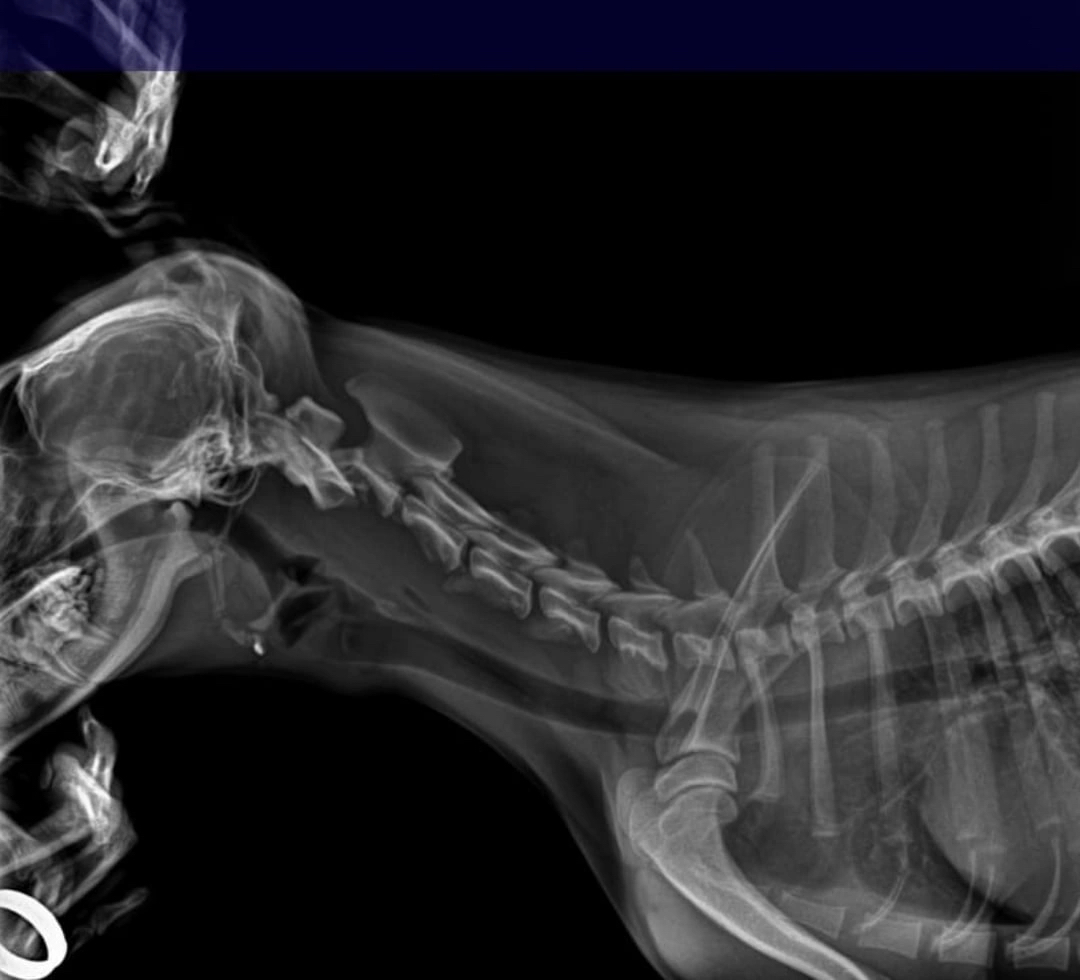

У собаки сложная травма позвоночника и перелом тазобедренной кости.

Но сутки его почему то готовят к операции на бедре, а сломанная шея болтается сама по себе.

Пёс с каждой минутой всё хуже и хуже себя чувствовал, имел гипертонус, мерцание зрачка, сбивчивость дыхания и сознания. Обусловлено это неправильной транспортировкой при выполнении манипуляций(пес кусачка и в стаце его видимо фиксировали) - итог более сильное смещение позвонков и полное защемление нервов позвоночника.